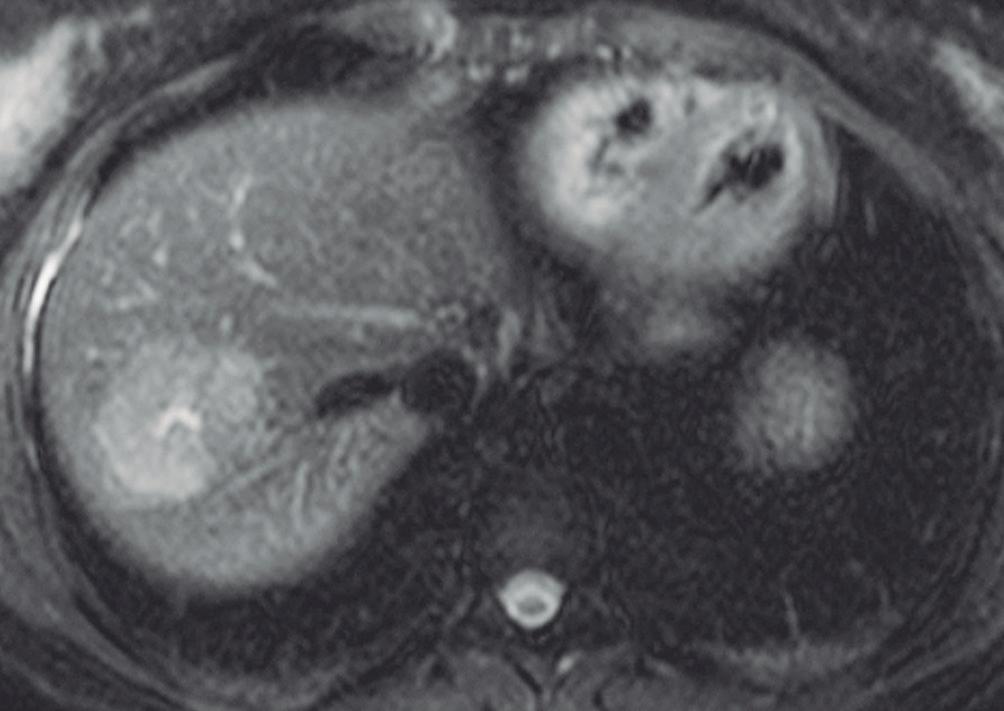

(Figura 1) En los hemangiomas de mayor tamaño el pasaje del contraste al centro de la lesión toma más tiempo e incluso no ocurre en aquellos más voluminosos.

En la RM los hemangiomas son lesiones con señal hipointensa en T1 e hiperintensa muy marcada en T2. Esta última característica los diferencia de otras lesiones benignas o malignas, con excepción de los quistes, que presentan señal más elevada debido a su contenido acuoso.1 El patrón de realce poscontraste es igual al que muestra la TC. (Figura 2) En la secuencia de difusión no presentan un patrón restrictivo, si bien pueden exhibir una señal brillante en valores b altos (parámetro que pondera la difusión); esto se debe al efecto brillo T2 y no a la restricción verdadera, por lo que el mapa del coeficiente de difusión aparente (ADC, por sus siglas en in-

A

glés) muestra señal y valores altos. En estudios con CHE son hipointensos en fase hepatobiliar ya que carecen de hepatocitos. Una potencial causa de error puede ocurrir en algunos hemangiomas pequeños que presenten un refuerzo precoz importante y que en fase de equilibrio (3 minutos) pueden presentarse hipointensos (pseudolavado). De esta manera podrían ser malinterpretados como un CHC.2 No obstante, la característica señal brillante de los hemangiomas en T2 es de utilidad para una tipificación correcta.

A: T1 post contraste en fase venosa portal; B, y fase de equilibrio; C: Muestran lesiones en segmentos IV y VI con una señal marcadamente hiperintensa en la secuencia T2 y

Lesiones benignas localizadas en el hígado desde la mirada de las imágenes Mariano Volpacchio Figura 1. Hemangioma en tomografía computada. Imágenes axiales de la TC sin contraste Figura 2. Hemangioma en la RM. Imágenes axiales de la RM en secuencia T2 con supresión grasa con el refuerzo similar a las estructuras vasculares de aspecto globular y progresivo en sucesivas fases. Nótese la heterogeneidad del hemangioma de mayor tamaño en segmento VI. A B C